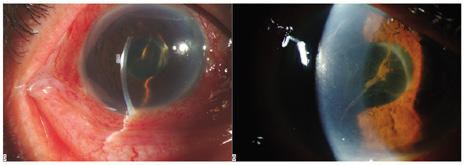

CONJUNCTIVAL FILTERING BLEB-ASSOCIATED ENDOPHTHALMITIS

This category of endophthalmitis is similar to acute postoperative endophthalmitis in that these patients manifest a sudden onset of pain, visual loss, conjunctival congestion, purulent bleb involvement, and the typical diagnostic features of acute-onset endophthalmitis (Fig. 8).10,11,104 Risk factors for this category of endophthalmitis include a history of conjunctivitis, contaminated topical glaucoma medications, the use of contact lenses, and inferior filtering bleb.10,104 The incidence of bleb-related endophthalmitis after a glaucoma-filtration procedure with mitomycin C may be higher than for trabeculectomy without antifibrotic agents.104 The organisms frequently involved in this type of endophthalmitis include streptococcal species8,71 and Hemophilus influenzae. Because of the frequency of these virulent organisms and the generally poor visual acuity outcomes, PPV and intraocular antibiotics are often considered as the initial approach for conjunctival filtering bleb-associated endophthalmitis.

Fig. 8. Delayed-onset endophthalmitis associated with glaucoma filtering blebs. Organisms invade the bleb initially and spread to involve intraocular fluids and tissues. This patient shows characteristic purulence of the filtering bleb, conjunctival congestion, hypopyon and fibrin in the pupil. Streptococcus pneumoniae was isolated from the vitreous specimen.

It is important to distinguish between a localized bleb infection (blebitis) and true endophthalmitis associated with an infected filtering bleb.11 The former category can be treated with intensive topical, subconjunctival, and possibly systemic antibiotics while the latter category can be treated in a manner similar to acute-onset postoperative endophthalmitis (Fig. 9).

Fig. 9. Bleb-associated endophthalmitis occurring two years following glaucoma filtering surgery. Left: Marked purulence of the bleb, hypopyon, and fibrin in the pupil. Visual acuity was reduced to hand motion. The patient was treated with a vitreous tap and injected with intravitreal antibiotics. Right: Coagulase-negative staphylococcus was isolated from the vitreous. Final visual acuity was 20/400 because advanced glaucomatous disease limited visual recovery.